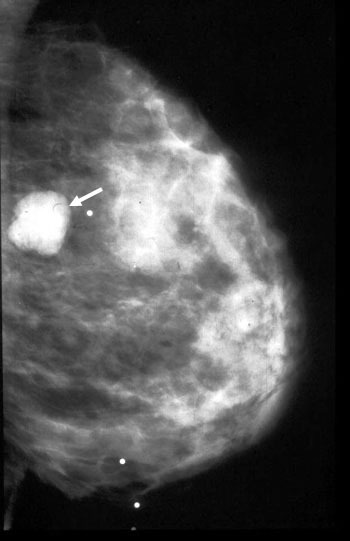

Mamografi (Altın Standart):

Mikrokalsifikasyonlar: LR (+) 15.0. (Özellikle pleomorfik/dallanan tipteyse)

Spiküle Kitle: LR (+) > 20.0.

Meme Ultrasonografisi (USG):

Dens memelerde (Genç hastalar) mamografinin kör noktalarını aydınlatır.

Solid vs Kistik ayrımı: Kist ise LR 0 (Benign), Solid ve damarlanma artışı varsa LR (+) 10.0.

"Mamografide Spiküle (Dikenli) Kitle Varlığı ile Luminal A Alt Tip Meme Kanseri Arasında Bir Korelasyon Var mıdır?"

Bu çalışma, mamografik görüntüleme bulguları ile meme kanserinin moleküler alt tipleri arasındaki biyolojik bağı incelemektedir. 317 hastanın retrospektif analizi üzerinden yapılan çalışma, fenotip (görüntü) ile genotip (moleküler belirteçler) arasındaki ilişkiyi Bayesyen bir olasılık çerçevesinde sunar.

Luminal A Dominansı: Spiküle (kenarları ışınsal uzantılı) kitlelerin %71'i Luminal A alt tipi olarak sınıflandırılmıştır.

Olasılık Oranı (Odds Ratio): Luminal A alt tipindeki kitlelerin, diğer alt tiplere oranla mamografide spiküle görünüm sergileme olasılığı 10.3 kat daha fazladır (p < 0.001).

İyi Prognoz İşareti: Spiküle marjlar, genellikle tümör hücrelerinin çevre dokuyla (stroma/yağ dokusu) etkileşimini ve düşük dereceli (low-grade) progresyonu gösterir. Bu durum, spiküle kitlelerin neden daha iyi bir prognoza işaret ettiğini açıklar.